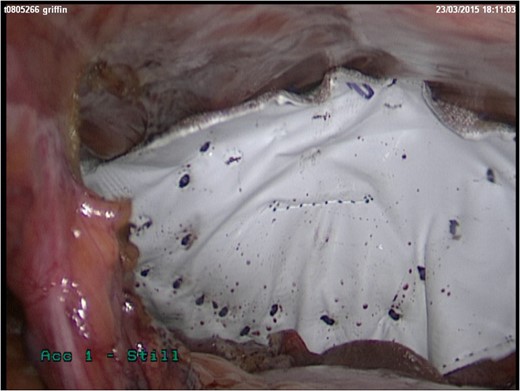

She represented later to our unit with recurrent vomiting. Her investigations revealed a raised lactate and acidosis on arterial blood gas. There was a concern for gastric ischaemia; the decision was taken to proceed to theatre. Given that she was haemodynamically stable with no peritonitis, we chose to operate using a laparoscopic approach. Surgery was performed through four laparoscopy (2Â Ă—Â 11 mm, 2Â Ă—Â 5 mm). A diagnosis of Morgagni hernia was made (Fig. 2). Inside the hernial sac was the transverse colon, the greater curvature of the stomach with a partial gastric volvulus (Fig. 3). The hernia was reduced with the viscera still viable but the sac could not be excised. The defect was repaired with a 6Â Ă—Â 10 cm composite mesh with an absorbable tic fixation on the diaphragm (Fig. 4). No drain was inserted, and the operation time in total was 45 minutes.